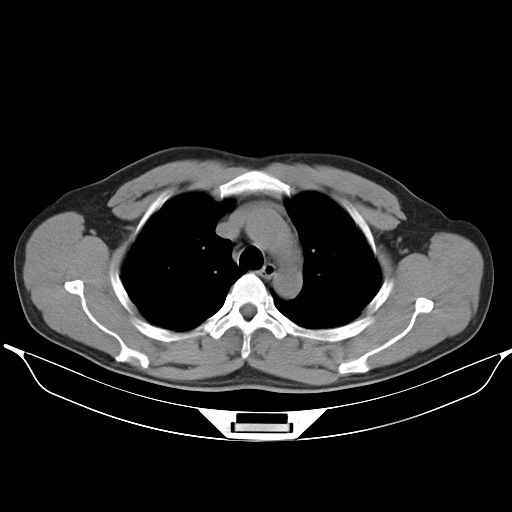

标题: CT25490:男,40岁,体检发现;无其它不适。 [打印本页]

标题: CT25490:男,40岁,体检发现;无其它不适。

倾向于结核

多考虑结核。

考虑结核

考虑肺霉菌病。

考虑右下肺周围性肺癌并肺内多发转移,纵隔淋巴结转移!

支持 !考虑右下肺周围性肺癌并肺内多发转移,纵隔淋巴结转移,(气管前腔静脉后,隆突下,主动脉弓下都有了)

感染性肉芽肿